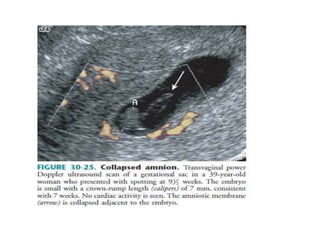

4. Amnion and yolk sac criterion

 Visualization of the amnion in the absence of a

sonographically demonstrable embryo after 7

weeks’ MA is abnormal and diagnostic of the non

viable pregnancy.

 The amnion is visualized after the embryo. So it

should never be visualized in the absence of the

embryo.

 Other findings that may be useful in the

diagnosis of the embryonic demise include a

collapsing, irregularly marginated amnion and yolk

sac calcification.